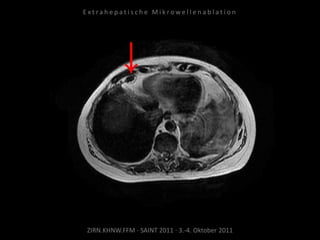

Ausgangsbildgebung:

CT vom 21.12.2009

Bildgebung vor MWA:

CT vom 14.07.2010

Metastase lateral der linken Niere

nahe Colon descendens progredient.